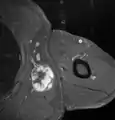

Fig. 7 MRI of myxoid liposarcoma of high grade, in the left axillary region of 40 year old man, highlighted by its white color, in this horizontal section of the tumor.